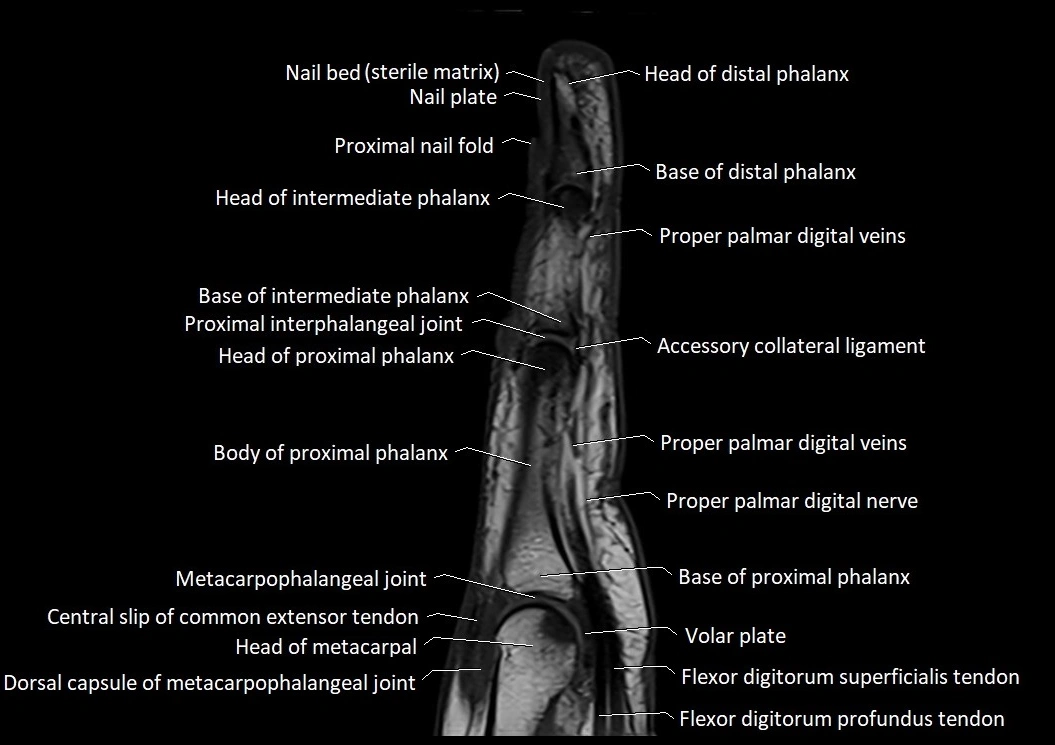

MRI images

image